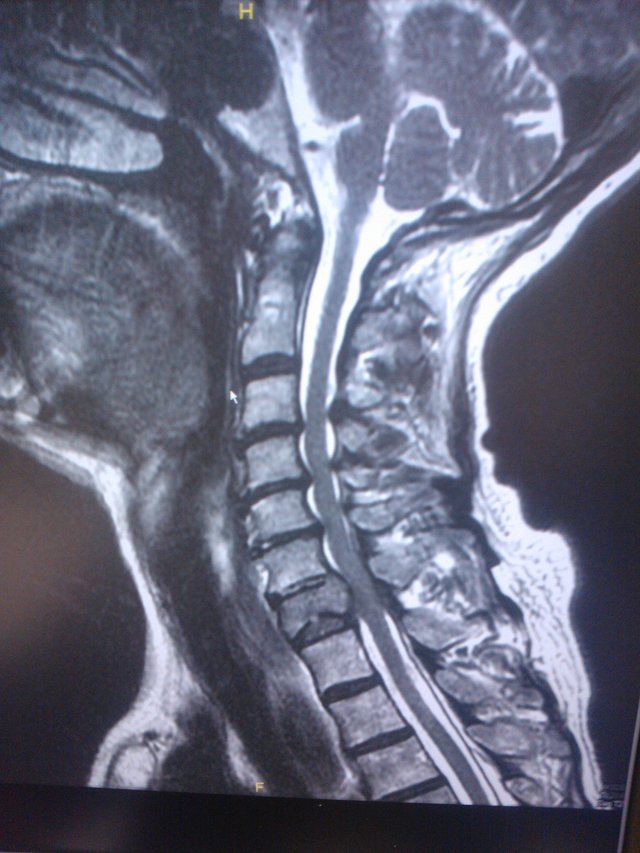

Young patient came to see me with weakness of her arms and legs

She was dropping objects from her hands and her walking was quite off balance

She was found on MRI to have a tumor in her spine along her neck compressing her spinal cord

Fortunately after a complex surgery, I was able to stabilize her spine and her strength returned over timeIMG_4663.JPG